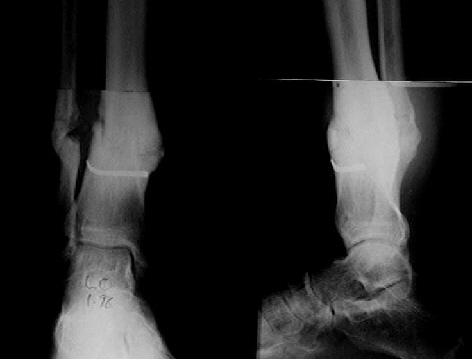

It seem a stiff pseudarthrosis. I will do a axial correction and lengthening if necessary with Ilizarov frame without any corticotomy. Probability of success will be 100% and relapse of infection 0%. You can see one case attached.